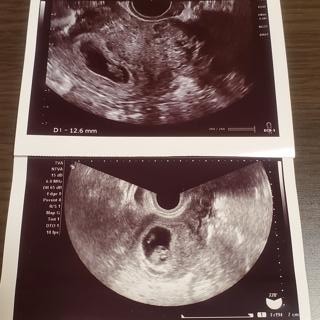

上が8w2d、下が8w3d、別の病院です。

前日は12.6mmで小さいのではないかと不安になっていたのですが、翌日の転院先では14mm以上あると言われてホッとしました。(1日しか違わないのに別の人のエコー写真みたい)

赤ちゃんの角度や測り方によっても変わると言われたので、正確ではないのと誤差も結構あるんだなと勉強になりました。

心臓もしっかり動いていて、「とっても元気」と言ってもらえました。

2cm程の筋腫が2つあるようですが、場所的に問題ないと言われました。